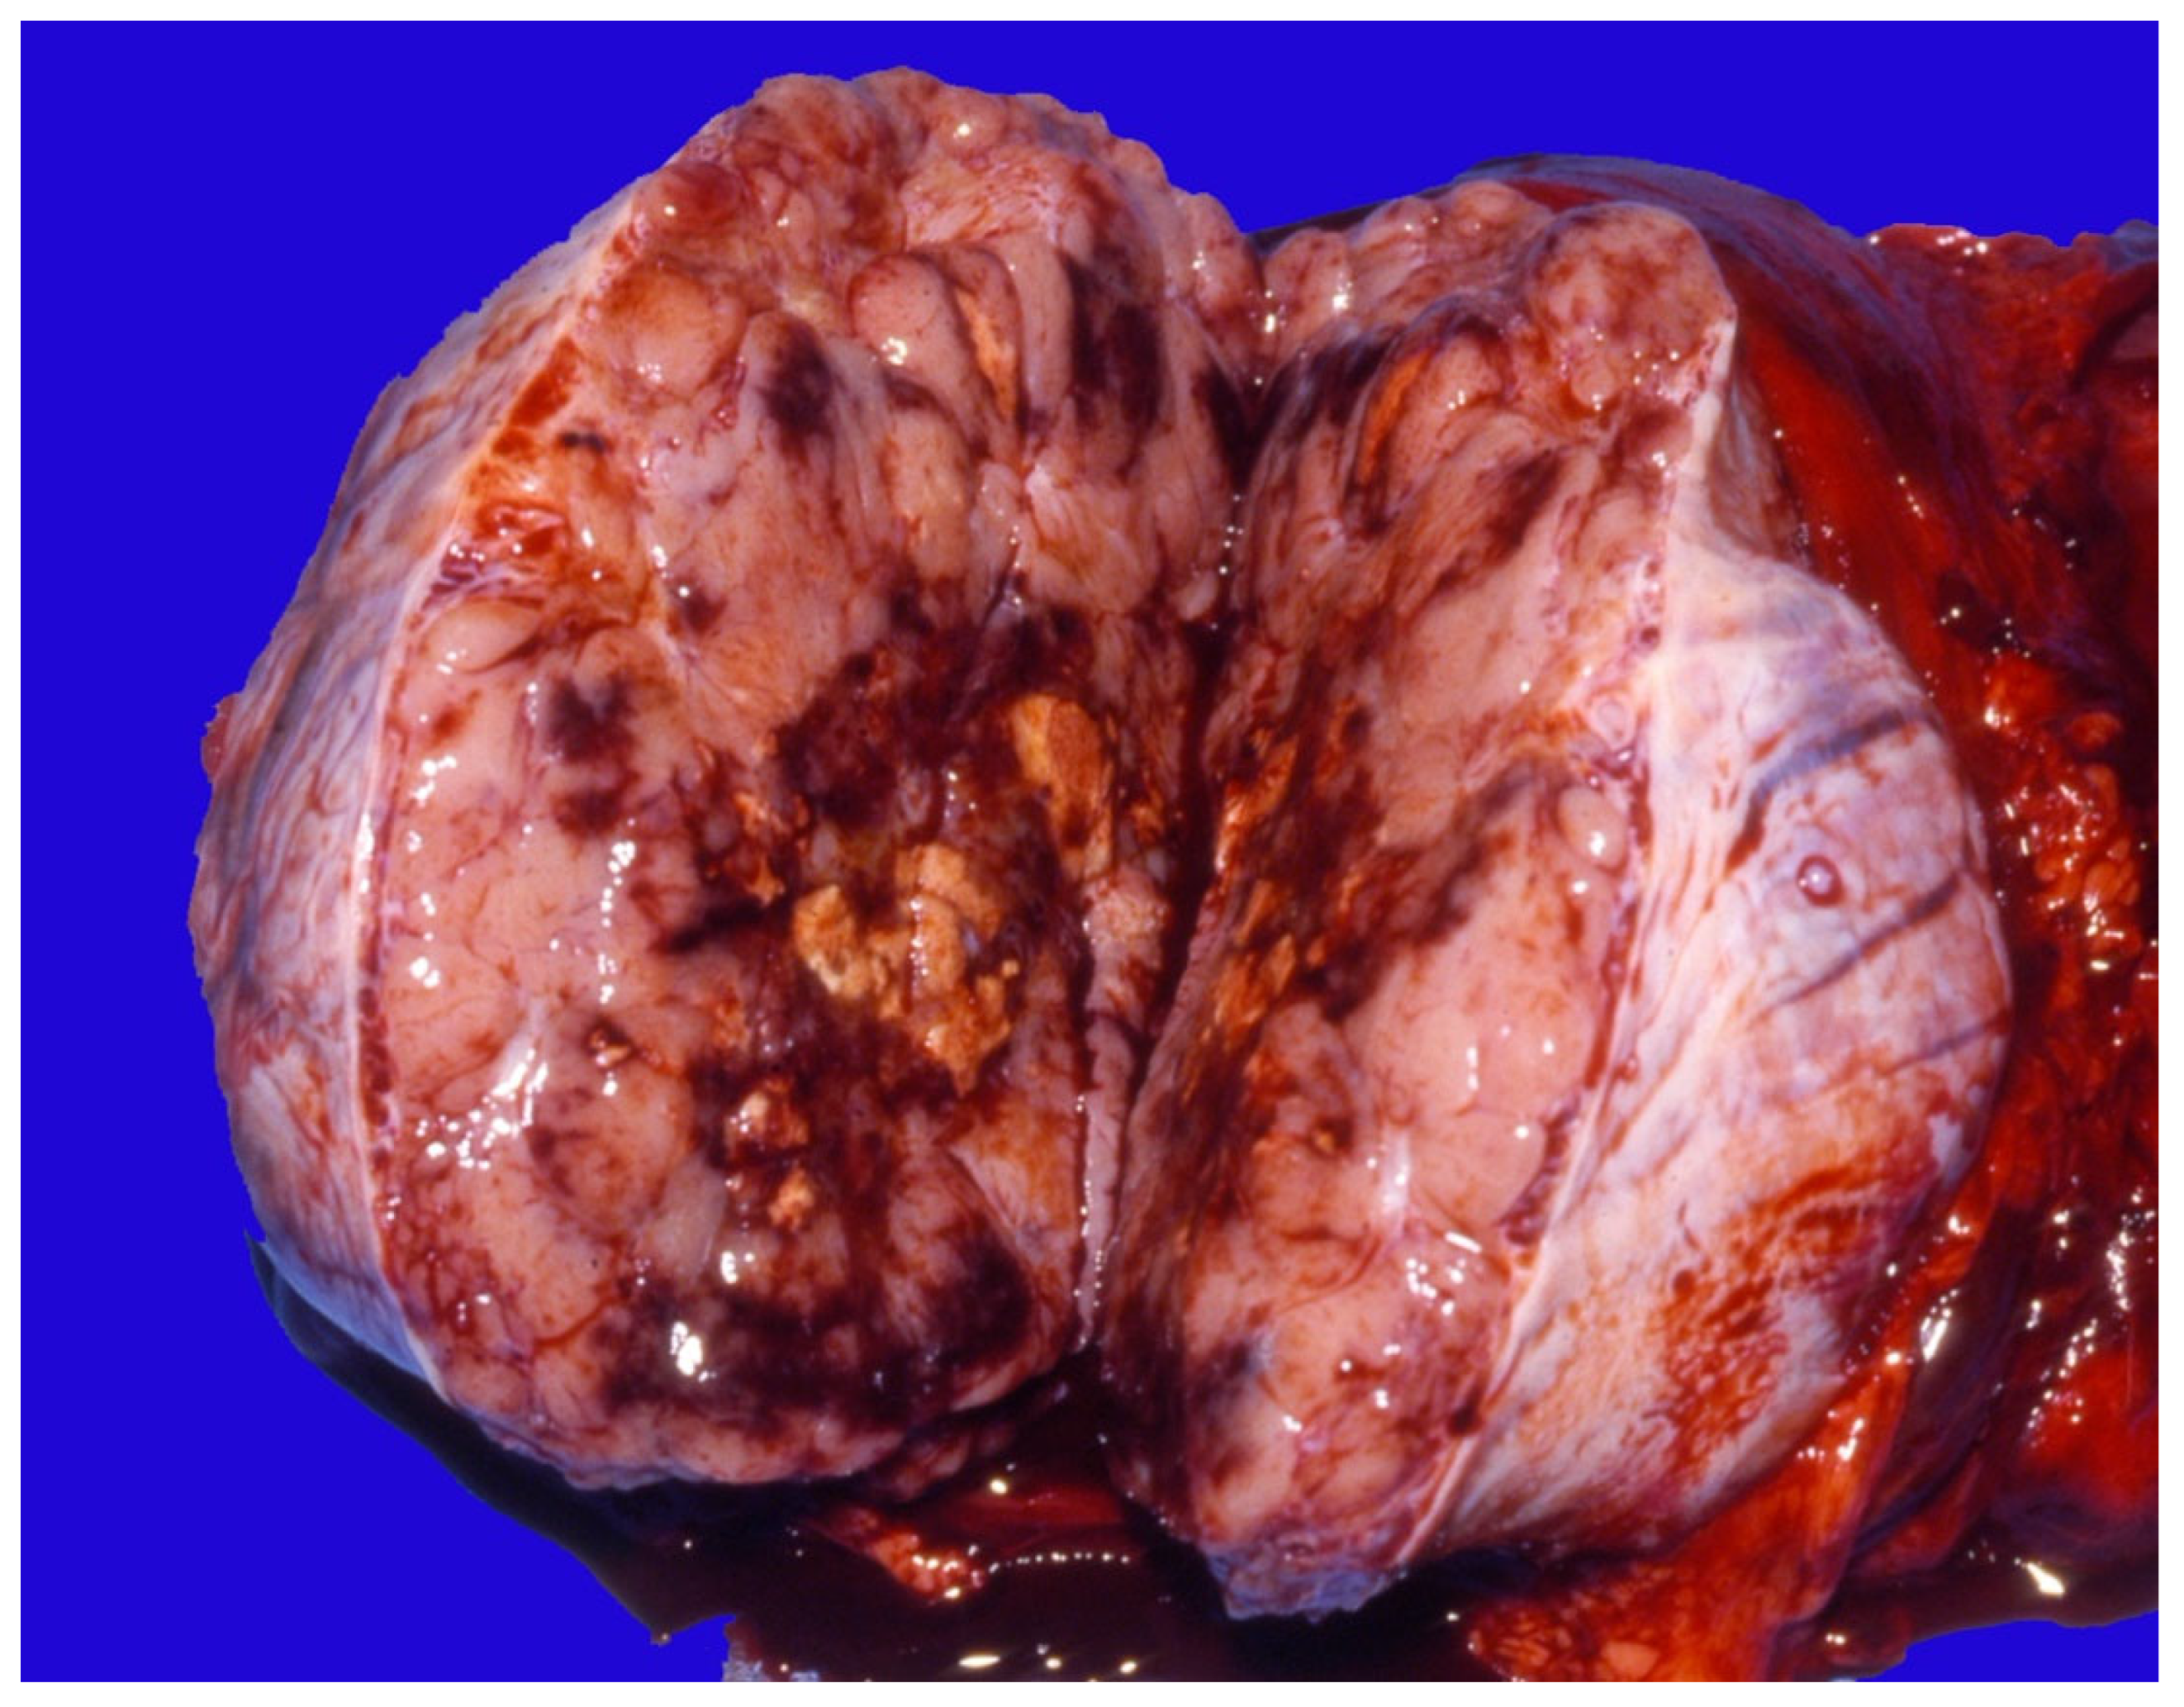

5.4. Scrotal and Testicular Tumors